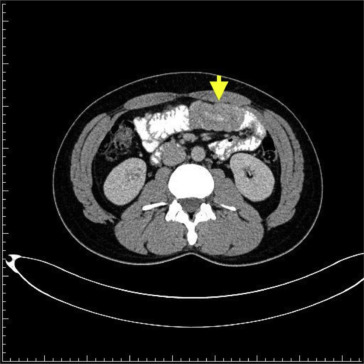

On histopathology, this polypoid lesion shows a hamartomatous intestinal polyposis with the distinct feature of an arborizing framework of smooth muscle within the muscularis mucosae (Fig. 4 ), a typical finding of the polyp of PJS. Owing to the absence of involved family members of the PJS patient, a lack of mucocutaneous pigmentation, and the presence of a solitary polyp with the characteristic histopathologic appearance of PJS, solitary or sporadic PJP is identified [1] .

Arborizing framework of smooth muscle within the muscularis mucosae.

Figure 4.